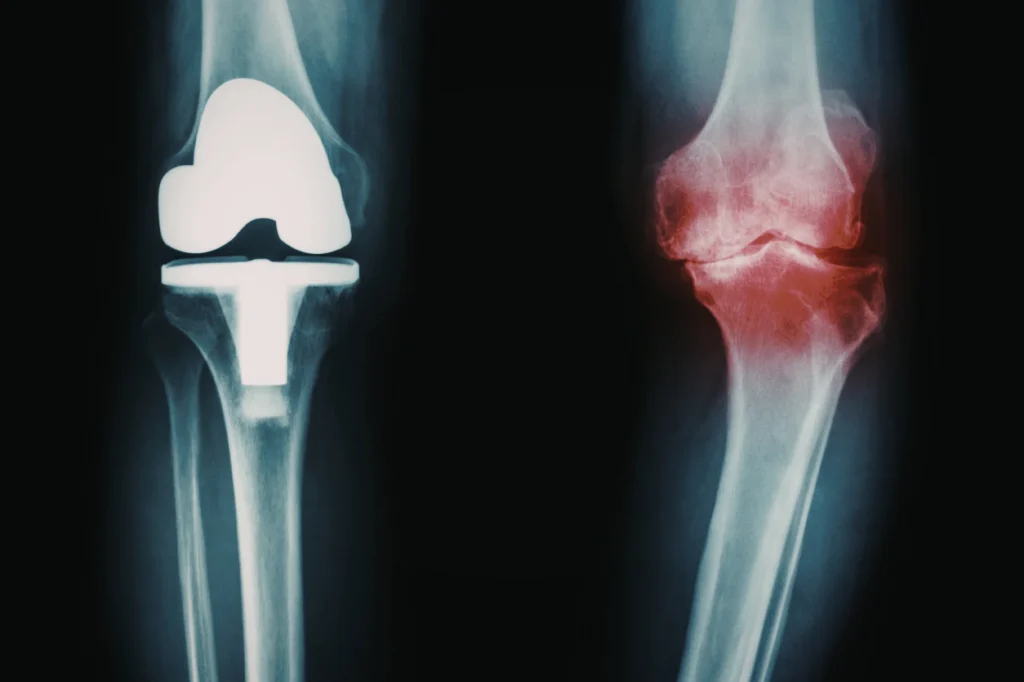

Osteoarthritis is the most common form of arthritis, affecting millions of people worldwide. It is a degenerative joint disease characterized by the breakdown of articular cartilage. This smooth, cushion-like tissue covers the ends of the bones in a joint. In a healthy knee, this cartilage allows the thighbone (femur) and shinbone (tibia) to glide effortlessly against each other. When this protective layer wears away, the bones can rub together. This friction causes chronic pain, stiffness, and swelling.

However, as the disease progresses, these conservative treatments may eventually fail to provide adequate relief. When the pain becomes severe, persistent, and limits daily activities, knee replacement surgery may become a consideration. The ultimate goal of this surgery is to relieve pain, restore function, and improve the patient’s overall quality of life.